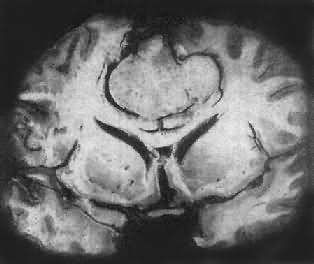

肉眼观,肿为数厘米的结节至巨大块状。分化较好的肿,境界不清;而分化程度较低的肿则境界分明。体灰白色。质地视肿内胶质纤维多少而异,或硬、或软、或呈胶冻状外观,并可形成大小不等的囊腔。由于肿的生长、占位和邻近脑细胞的肿胀,脑的原有结构因受挤压而扭曲变形(图16-23)。

图16-23 星形胶质细胞

左大脑半球肿胀,肿边界不清,部分呈胶冻状